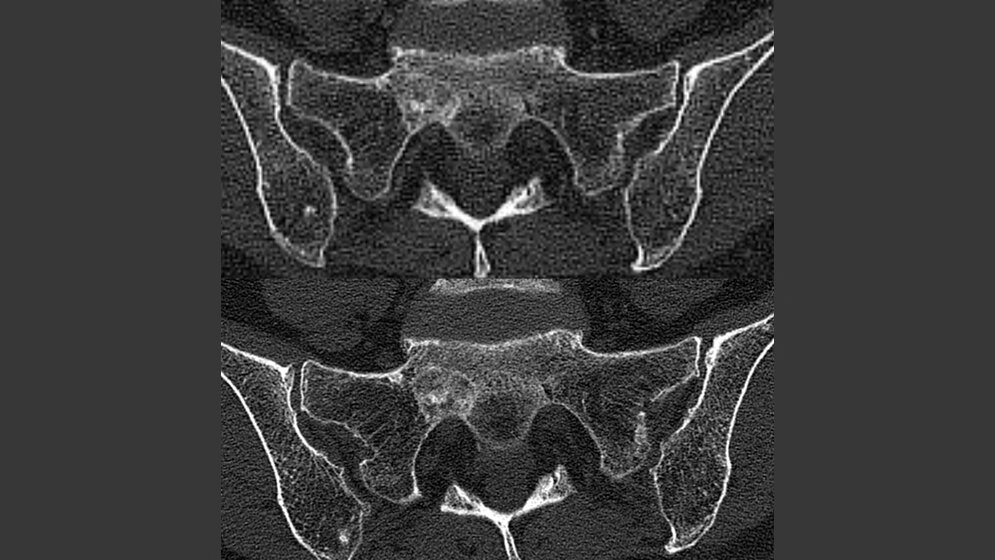

In der aktuellen Studie wurden die PC-CT-Bilder von Knochenmetastasen bei Patientinnen mit fortgeschrittenen Brustkrebserkrankungen von mehreren Ärzten beurteilt und mit konventionellen CT-Aufnahmen verglichen. Die mithilfe der neuen Technik generierten Bilder wurden durchgehend als schärfer und detailreicher beurteilt. Insbesondere Veränderungen an sehr feinen Strukturen wie etwa den Knochenbälkchen (Trabekeln) waren besser zu erkennen.

„Durch sein neuartiges Detektorsystem hat das PC-CT deutlich schärfere Augen als die herkömmlichen Geräte. Daher können wir damit Bilder in höherer räumlicher Auflösung erzeugen, als es bisher möglich ist“, erläutert Heinz-Peter Schlemmer, Leiter der Radiologie im DKFZ, und ergänzt. „Oder wir können Bilder mit der gleichen Qualität generieren wie mit dem konventionellen CT – bei deutlich niedrigerer Strahlendosis.“ Das liegt an der höheren Empfindlichkeit und am günstigeren Signal-Rausch-Verhältnis der neuen Detektoren. So eröffnet die neue Technik in Zukunft auch aussichtsreiche Perspektiven für viele weitere Indikationen, wie etwa Screening-Untersuchungen oder Bildgebung bei Kindern.